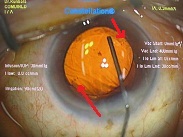

今日は水晶体亜脱臼による緑内障発作の患者様がいらっしゃり、お昼休みに緊急手術をさせて頂きました。

先日ハードレンズを処方した方の写真です。